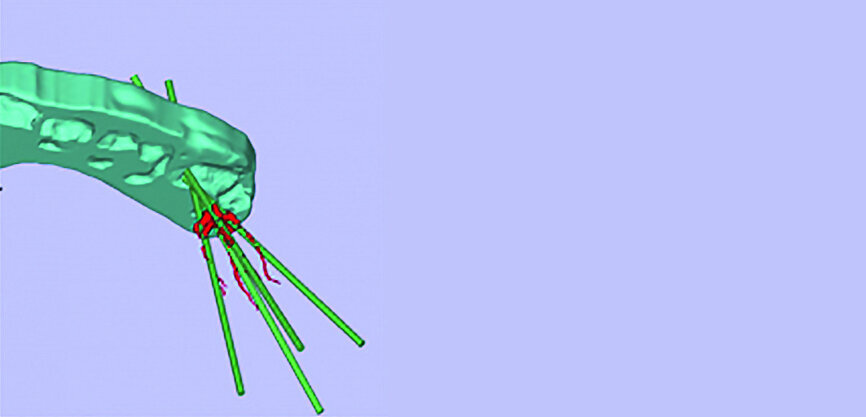

Figs. 11a–c : Depuis la gauche : plan de traitement virtuel pour un accès endodontique guidé par scanner (CT-GEA). La dent à traiter est segmentée par le scanner volumique, des trajets d’accès idéaux sont tracés au travers de la face occlusale de la dent, et un guide de forage CT-GEA est imprimé en 3D.